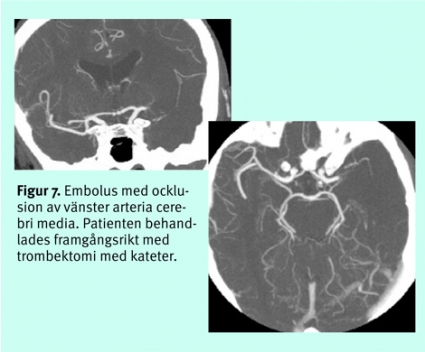

Akut tomografisk kärldiagnostik. Eftersom den akuta behandlingen riktar sig mot artärocklusioner, får snabba, låginvasiva angiografiska tekniker stor relevans. Stora studier av betydelsen av ocklusioner för intravenös trombolys saknas ännu, men intuitivt förefaller naturligtvis sådan terapi inte gagna patienter utan synlig tromb eller embolus. Ocklusioner som omfattar både karotissifonens topp och första delarna av arteria cerebri anterior och media har små chanser till rekanalisering med intravenös terapi [3].

Den senaste tidens utveckling av DT-angiografi med multidetektorteknik gör det möjligt att morfologiskt kartlägga cerebrala artärer från aortabågen ut till 2:a eller 3:e ordningens förgreningar. DT-angiografi från aortabågen till hjärnan är en snabb metod; avbildningen tar under 1 minut, medan bearbetningen och bedömningen av bilderna kräver 5–30 minuter. DT-angiografi används allt oftare för akut bedömning av embolikälla i karotis och embolier i intrakraniella kärl (Figur 7). DT-angiografi används också som första led i utredningen vid många universitetskliniker för att påvisa aneurysm vid subaraknoidalblödning.